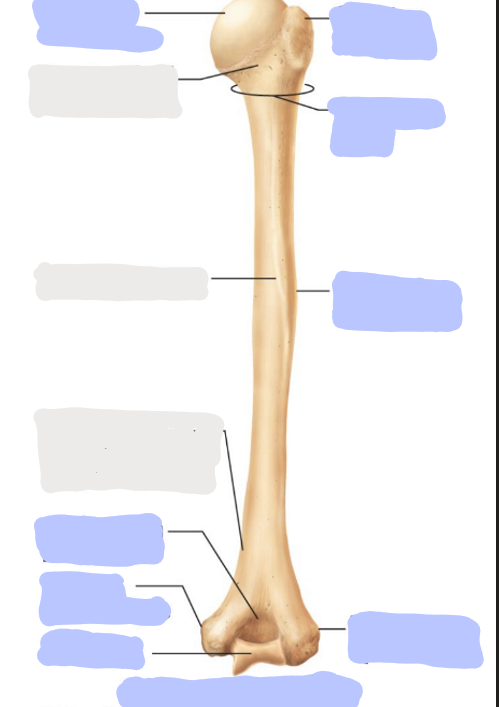

What is this picture of?

Posterior view of the right humerus

What is here?

Where is the Head of the humerus?

What is here?

Where is the Surgical Neck of the humerus?

What is here?

Where is the Greater Tubercle of the humerus?

What is here?

Where is the Deltoid Tuberosity of the humerus?

What is here?

Where is the Trochlea of the humerus?

What is here?

Where is the Lateral Epicondyle of the humerus?

What is here?

Where is the Medial Epicondyle of the humerus?

What is here?

Where is the Olecranon Fossa of the humerus?